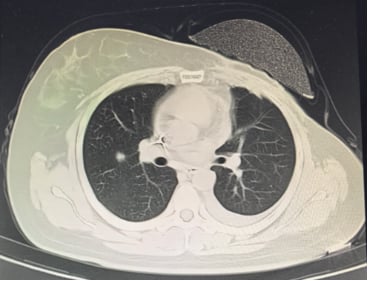

患者接受了规范的初始治疗:手术(左乳单切+SLNB+ALND),辅助化疗(AC-T*8周期),辅助放疗(患侧胸壁+锁骨上下区,50Gy/2Gy/25次),以及内分泌治疗(OFS+来曲唑)。2023年3月,为了强化治疗效果,医生为她加用了阿贝西利进行强化内分泌治疗。然而,尽管进行了积极治疗,疾病的进展依然迅速。2025年1月复查时疾病稳定,但仅两个月后,2025年3月强化内分泌治疗结束后,2025年4月复查就提示肺转移可能。胸部CT、骨扫描、头颅+腰椎CT等影像学检查均显示多发可疑病灶。最终,2025年5月的复查确诊为左乳癌术后肺、肝、左侧胸膜、骨转移,肝脏穿刺病理进一步证实为转移性腺癌,ER表达降至13%中+,PR阴性,HER2(2+),FISH阴性,再次确认HER2低表达。

然而,医学的希望之光并未熄灭。在绝境中,医生为患者调整了二线治疗方案——使用德曲妥珠单抗(DS8201)。令人欣喜的是,经过5个周期的治疗,患者症状明显缓解,病情得到了有效控制。这个案例再次证明了创新药物在晚期癌症治疗中的巨大潜力。